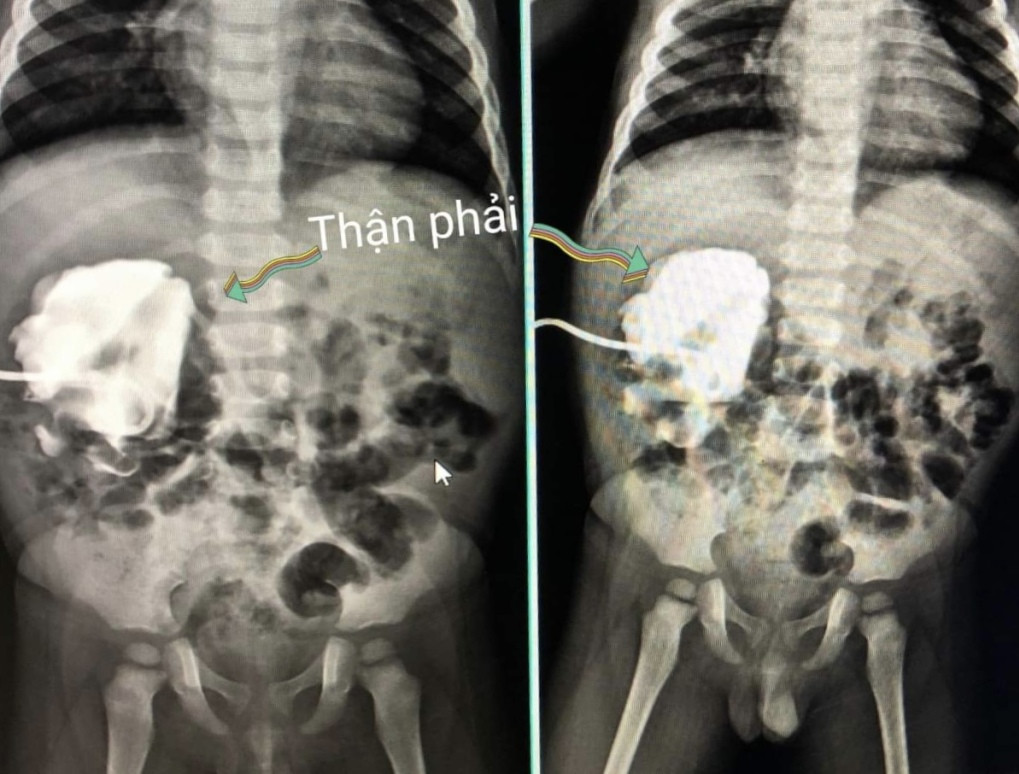

Theo TS.BS Liên, kết quả siêu âm cho thấy bé trai này chỉ có một quả thận, quả còn lại dù có nhưng đã bị teo bẩm sinh. Gần 1 năm nay, trẻ đi tiểu rất ít nhưng bàng quang lại luôn trong tình trạng cạn khô. Do không đi tiểu được nên quả thận còn lại bị suy, ứ nước, có bong bóng trên thận.

Đáng chú ý, quả thận này bị ứ nước nặng, giãn to chiếm nửa ổ bụng và đó chính là nguyên nhân gây nên tình trạng trẻ bị chướng bụng, căng cứng.

Các bác sĩ kết luận bệnh nhi bị đa dị tật hệ tiết niệu, thận teo nhỏ, thận trái hẹp niệu quản nhiều đoạn bất thường. Để cứu được chức năng thận còn lại, trẻ đã được chỉ định phẫu thuật nội soi tạo hình niệu quản.